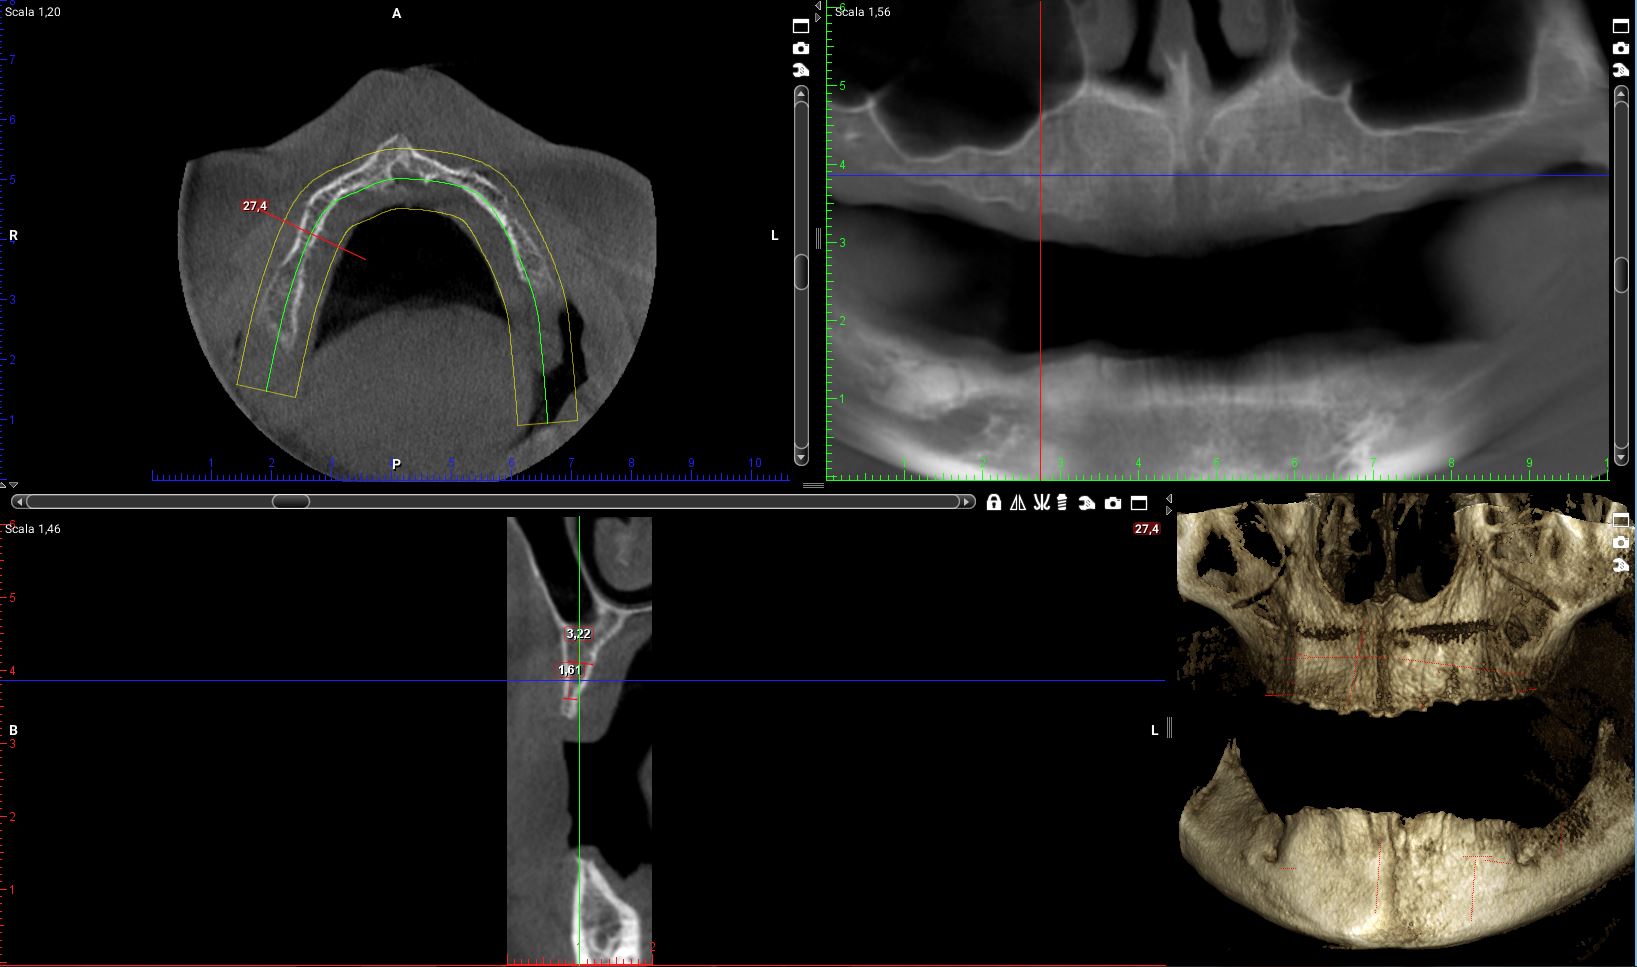

Ora riprendiamo i tagli della cone-beam della mia paziente in corrispondenza delle zone dove dovrò posizionare i quattro impianti.

Impianto distale di destra:la cresta è larga molto meno di 4mm per tutta la sua estensione in altezza. E di lì l’impianto ci deve passare!

il programma di progettazione, che tra l’altro fornisce una bella area di sicurezza intorno al volume della fixture, dice “NON SI PUO”!

Impianto mesiale di destra:

se vogliamo ricercare uno spessore di cresta che superi i 4 mm dobbiamo andare a 5mm dal pavimento del naso. Io non farei un carico immediato full-arch su un impianto da 5mm!

Anche qui il programma di simulazione dice “NON SI PUO’”!

Sulla sinistra e pure peggio!